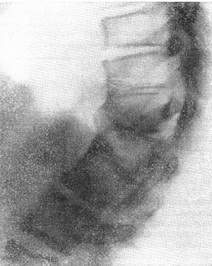

До аномалій розвитку хребта відносять також більшу частину випадків спондилолиза (див.). При спонділолизі, який буває одно - і двостороннім, зазначається незрощення дужки в міжсуглобової області (рис. 19). Внаслідок цього при двосторонньому спонділолизі задня частина дужки з нижніми суглобовими відростками хребців виявляється відокремленою (мається тільки хрящове з'єднання) від ніжок дужки з верхніми суглобовими відростками. Коли має місце зсув тіла хребця, пов'язаного з ніжками дужки і верхніми суглобовими відростками, з нижнього тіла хребця, говорять вже про спондилолістезу (див.).